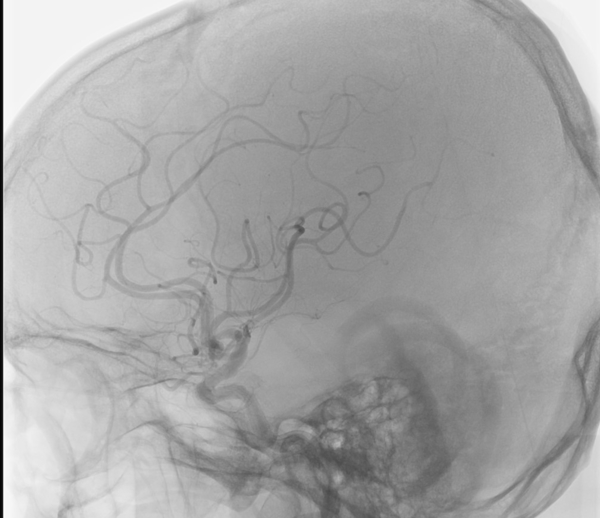

• Digital substraction angiography

shutterstock_2632199259.jpg

• Interventional X-ray

Radiology

Hybrid operating rooms (ORs) have many sources of imagery and footage, such as images from various imaging modalities (CT, MR, digital X-ray) and livestreams (endoscopes, interventional X-ray). This information is generated in various physical locations and needs to be available on displays for medical personnel in various screens in the OR.